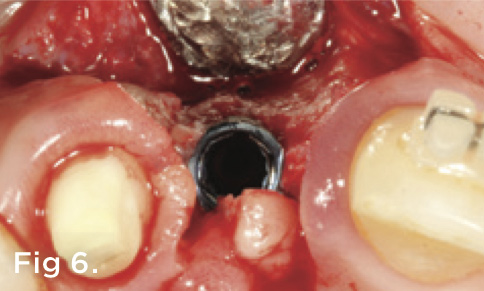

Fig 6. A papilla-sparing surgical incision design was used to preserve the interdental tissues during implant placement.

Figure 6

A 38-year-old Caucasian female patient presented with a high smile line and loss of the papilla between tooth No. 7 and edentulous adjacent site No. 8 (Figure 1). Understandably, the patient was unhappy and embarrassed about her esthetic condition. Her dental history revealed tooth replacement of No. 8 with an implant that eventually failed. The site had been previously bone grafted upon implant removal. She was given a composite pontic No. 8 bonded to a tooth No. 7 composite veneer as a transitional restoration. The implant was positioned too close to the proximal surface of tooth No. 7, which stripped the periodontal attachment of the root and ultimately caused loss of the papilla (Figure 2). As previously outlined, the treatment sequence would be to first provide a provisional restorative solution to evaluate the projected outcomes and assess if the patient was willing to undergo orthodontic therapy. In this situation, a full-coverage crown No. 7 with a cantilevered pontic No. 8, with artificial acrylic gingiva to replace the lost papilla on the mesial aspect of tooth No. 7 was used as a transitional temporary prosthesis (Figure 3). In addition, a composite resin restoration was placed on the mesial aspect of tooth No. 9 to restore its individual tooth proportion and shape. The patient’s esthetic outcome could now be evaluated with restorative correction alone; it was therefore mutually determined that the correction of her deformity would best be served with additional orthodontic forced eruption therapy. A fixed orthodontic appliance (brackets) was bonded to the teeth and temporary prosthesis. The level of the interproximal pink acrylic was used as a therapeutic guide for the amount of forced eruption required as well as the alignment of the mesial papilla of No. 7 to that of the adjacent papillae height (Figure 4). Floss was used to elevate the amount of vertical movement achieved relative to the adjacent papilla tooth No. 9. Eventually, all the artificial pink acrylic was removed. (Note that the distal papilla on tooth No. 7 also comes more incisal—in fact, it is slightly excessive at the endpoint of treatment [Figure 5]). However, the distal papilla and midfacial tissues of tooth No. 7 can be reshaped through clinical crown lengthening toward the end of treatment prior to definitive restoration, thereby restoring the proper papilla height-to-tooth ratio of 40%. After stabilization of tooth No. 7 for a minimum of 6 months post-orthodontics, an implant was placed in site No. 8. A papilla-sparing incision design was used for flap elevation (Figure 6), bone allograft was used to further augment the facial aspect of the ridge simultaneously with implant placement (Figure 7), and a resorbable membrane was used for guided bone regeneration.